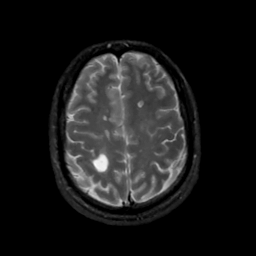

MR Study #10, April 28, 1991 -- Slice #38

[Home][Help][Clinical][Tour 1][Tour 2] Slice 38